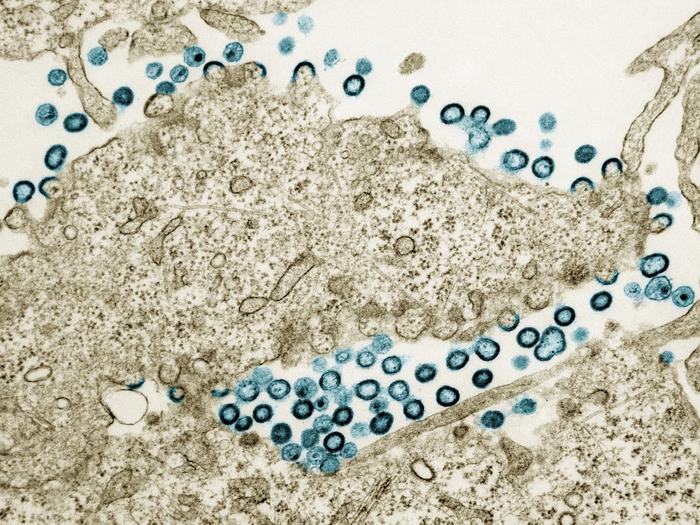

Transmission electron micrograph of HIV-1 virus particles (teal) budding and replicating from a segment of a chronically infected H9 cell (tan). Particles are in various stages of maturity; arc/semi-circles are immature particles that have started to form but are still part of the cell. Immature particles slowly change morphology into mature forms and exhibit the classic “conical or spherical-shaped core.” Image captured at the NIAID Integrated Research Facility in Fort Detrick, Maryland.